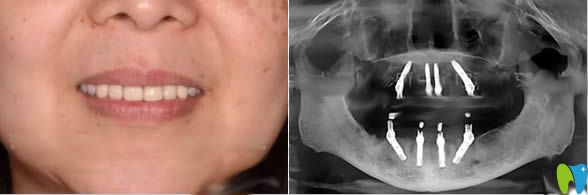

做完全口種植牙的照片及種牙后全景圖:

較后,說下我做完種植牙的感受吧,種牙前很是緊張,種牙過程的不適感可以忍受,種完后感覺像真牙一樣,但就是價格貴。具體宏康口腔科怎么樣,我個人覺得這家還是很靠譜的,這只是我個人的想法,大家可以參考哈!